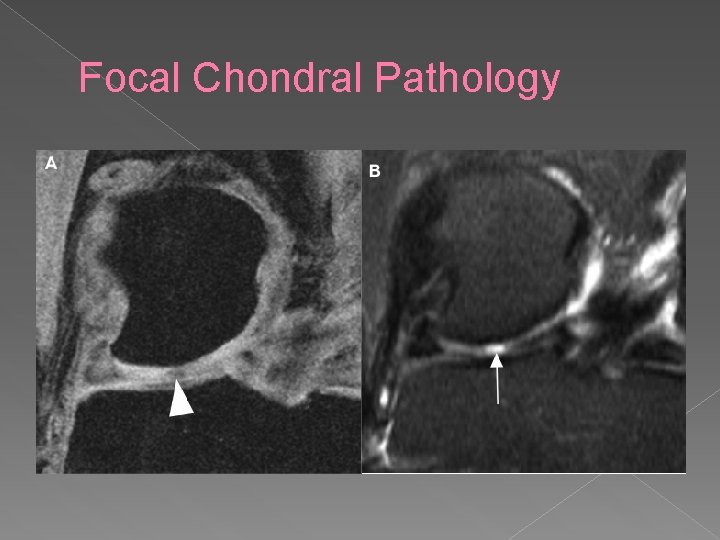

Focal Chondral Pathology